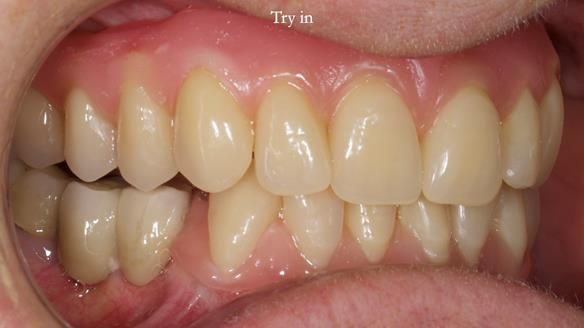

Mary’s upper occlusal plane wasn’t parallel to her interpupillary line, and she specifically wanted that natural asymmetry preserved. Rowan arranged the teeth beautifully, following the exact contour and character of her original smile.

For both the upper and lower dentures, we used Schottlander Enigma Life teeth. I’ve been using these since 2014 and they’ve been outstanding - the surface texture, colour depth, and light reflection are superb. When arranged to mirror the patient’s natural tooth positions, they look completely lifelike.